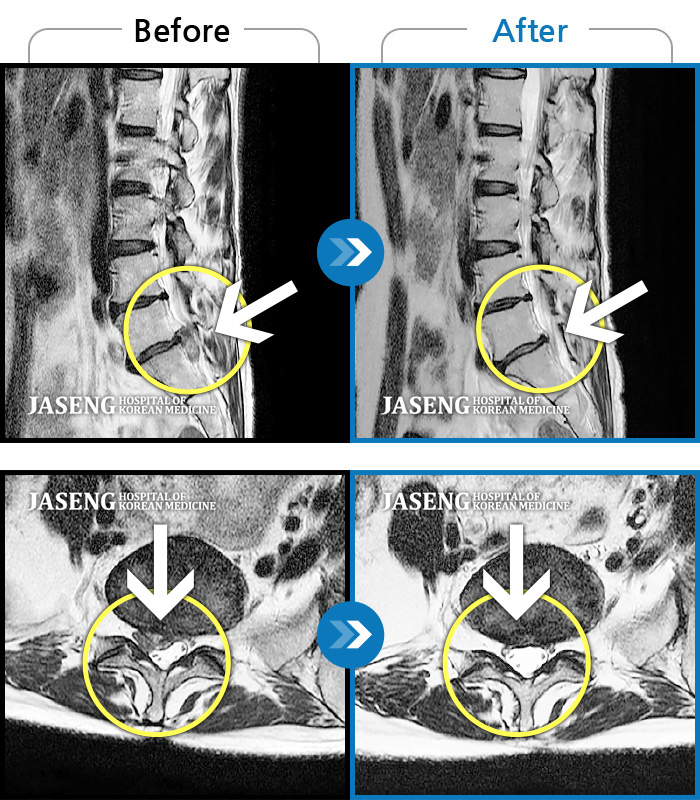

MRI 치료사례

발끝까지 저림이 계속되고, 앉거나 걸으면 증상 더 심해져 본원 내원